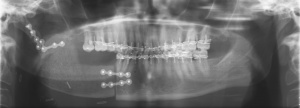

In einer extern angefertigten Panoramaschichtaufnahme bestand eine im Bereich apikal der Zähne 44-47 liegende und bis unterhalb des Processus condylaris reichende, ausgedehnte, mehrkammerige, scharf begrenzte Aufhellung. In direkter Lagebeziehung mit dem zystischen Prozess stellte sich apikal des Zahnes 46 der retinierte und verlagerte Zahn 45 dar.

Anamnestisch handelte es sich bei dieser Röntgenaufnahme um die erste Panoramaschichtaufnahme, die jemals bei dem Patienten angefertigt wurde (Abbildung 1).

Im Jahr 2013 stellte sich nach Zuweisung durch einen niedergelassenen MKG-Chirurgen eine 44jährige Patientin in der Ambulanz für MKG-Chirurgie des Bundeswehrkrankenhauses Hamburg vor. Anamnestisch bestand seit etwa drei Jahren ein Druck- und Schmerzempfinden im Bereich des rechten Kieferwinkels sowie der rechten Unterkieferseitenzähne. Daraufhin wiederholt durch den Hauszahnarzt angefertigte Bissflügel- und Einzelzahnaufnahmen hatten keinen pathologischen Befund erbracht. Erst als die Patientin auf Grund der persistierenden Beschwerden zu einem MKG-Chirurgen überwiesen worden war, wurde in einer Panoramaschichtaufnahme eine großvolumige Zyste im Bereich des rechten Unterkieferwinkels entdeckt (Abbildung 5).